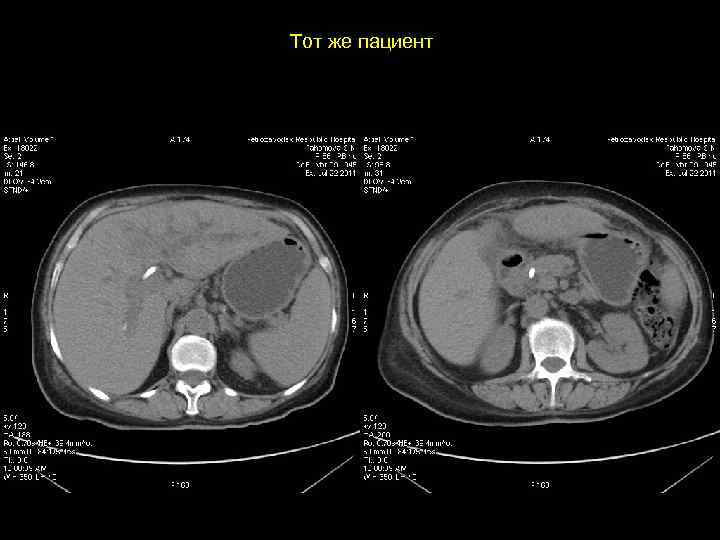

Тот же пациент